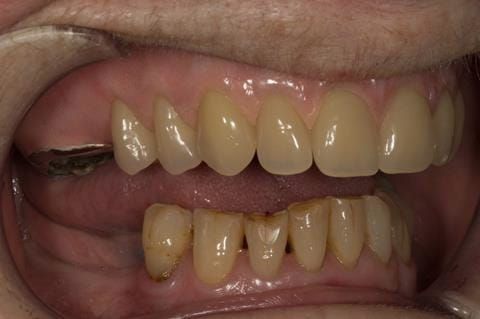

- Poorly fitting cobalt chromium based maxillary partial denture, which has been added to. This exhibited poor retention, stability and tissue fit (support). Unable to wear a new acrylic based denture.

- Eight mandibular anterior teeth worn incisal edges from now extracted maxillary anterior crowns. Gingivitis - owing to inadequate oral hygiene.

- Bruxism.